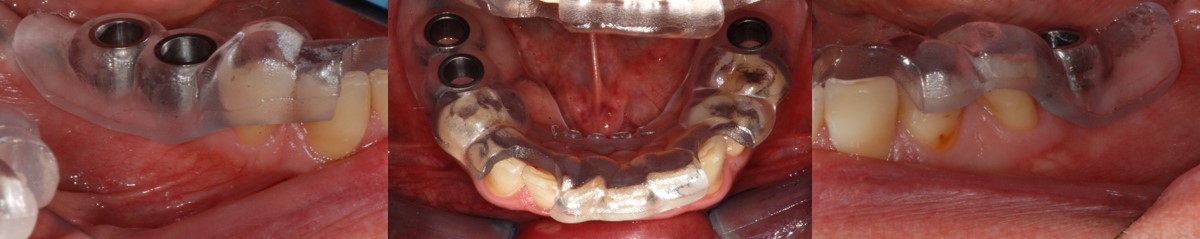

Si procedeva quindi il giorno dell’intervento all’esecuzione, su entrambi i lati, di un lembo sollevato a tutto spessore con un piccolo scarico distale. I lembi venivano poi ancorati alla mucosa geniena con delle suture, in modo da ottenere un miglior posizionamento della dima, la cui stabilità veniva garantita dagli elementi dentali presenti; ciò evitando che i tessuti molli potessero finire al di sotto della dima stessa, durante le fasi di fresatura. Si sceglieva di allestire i due lembi e di non eseguire una chirurgia flapless, per mantenere la maggior quantità possibile di tessuto cheratinizzato.

Posizionata la dima si passava alla preparazione dei siti implantari, con un kit di frese dedicato alla chirurgia guidata, e all’inserimento degli impianti (Naturactis, Lyra ETK, Sallanches, Francia). Queste fasi si svolgevano in modo veloce e sicuro, non dovendo pensare alla posizione finale, sia in senso verticale che orizzontale, degli impianti, essendo considerazioni già effettuate in fase di progettazione.

A completamento dell’intervento venivano avvitati gli abutment di guarigione selezionati e suturati i lembi.

Il controllo radiografico finale evidenziava il buon esito dell’intervento e la riproduzione fedele del progetto digitale iniziale (Figura 8).